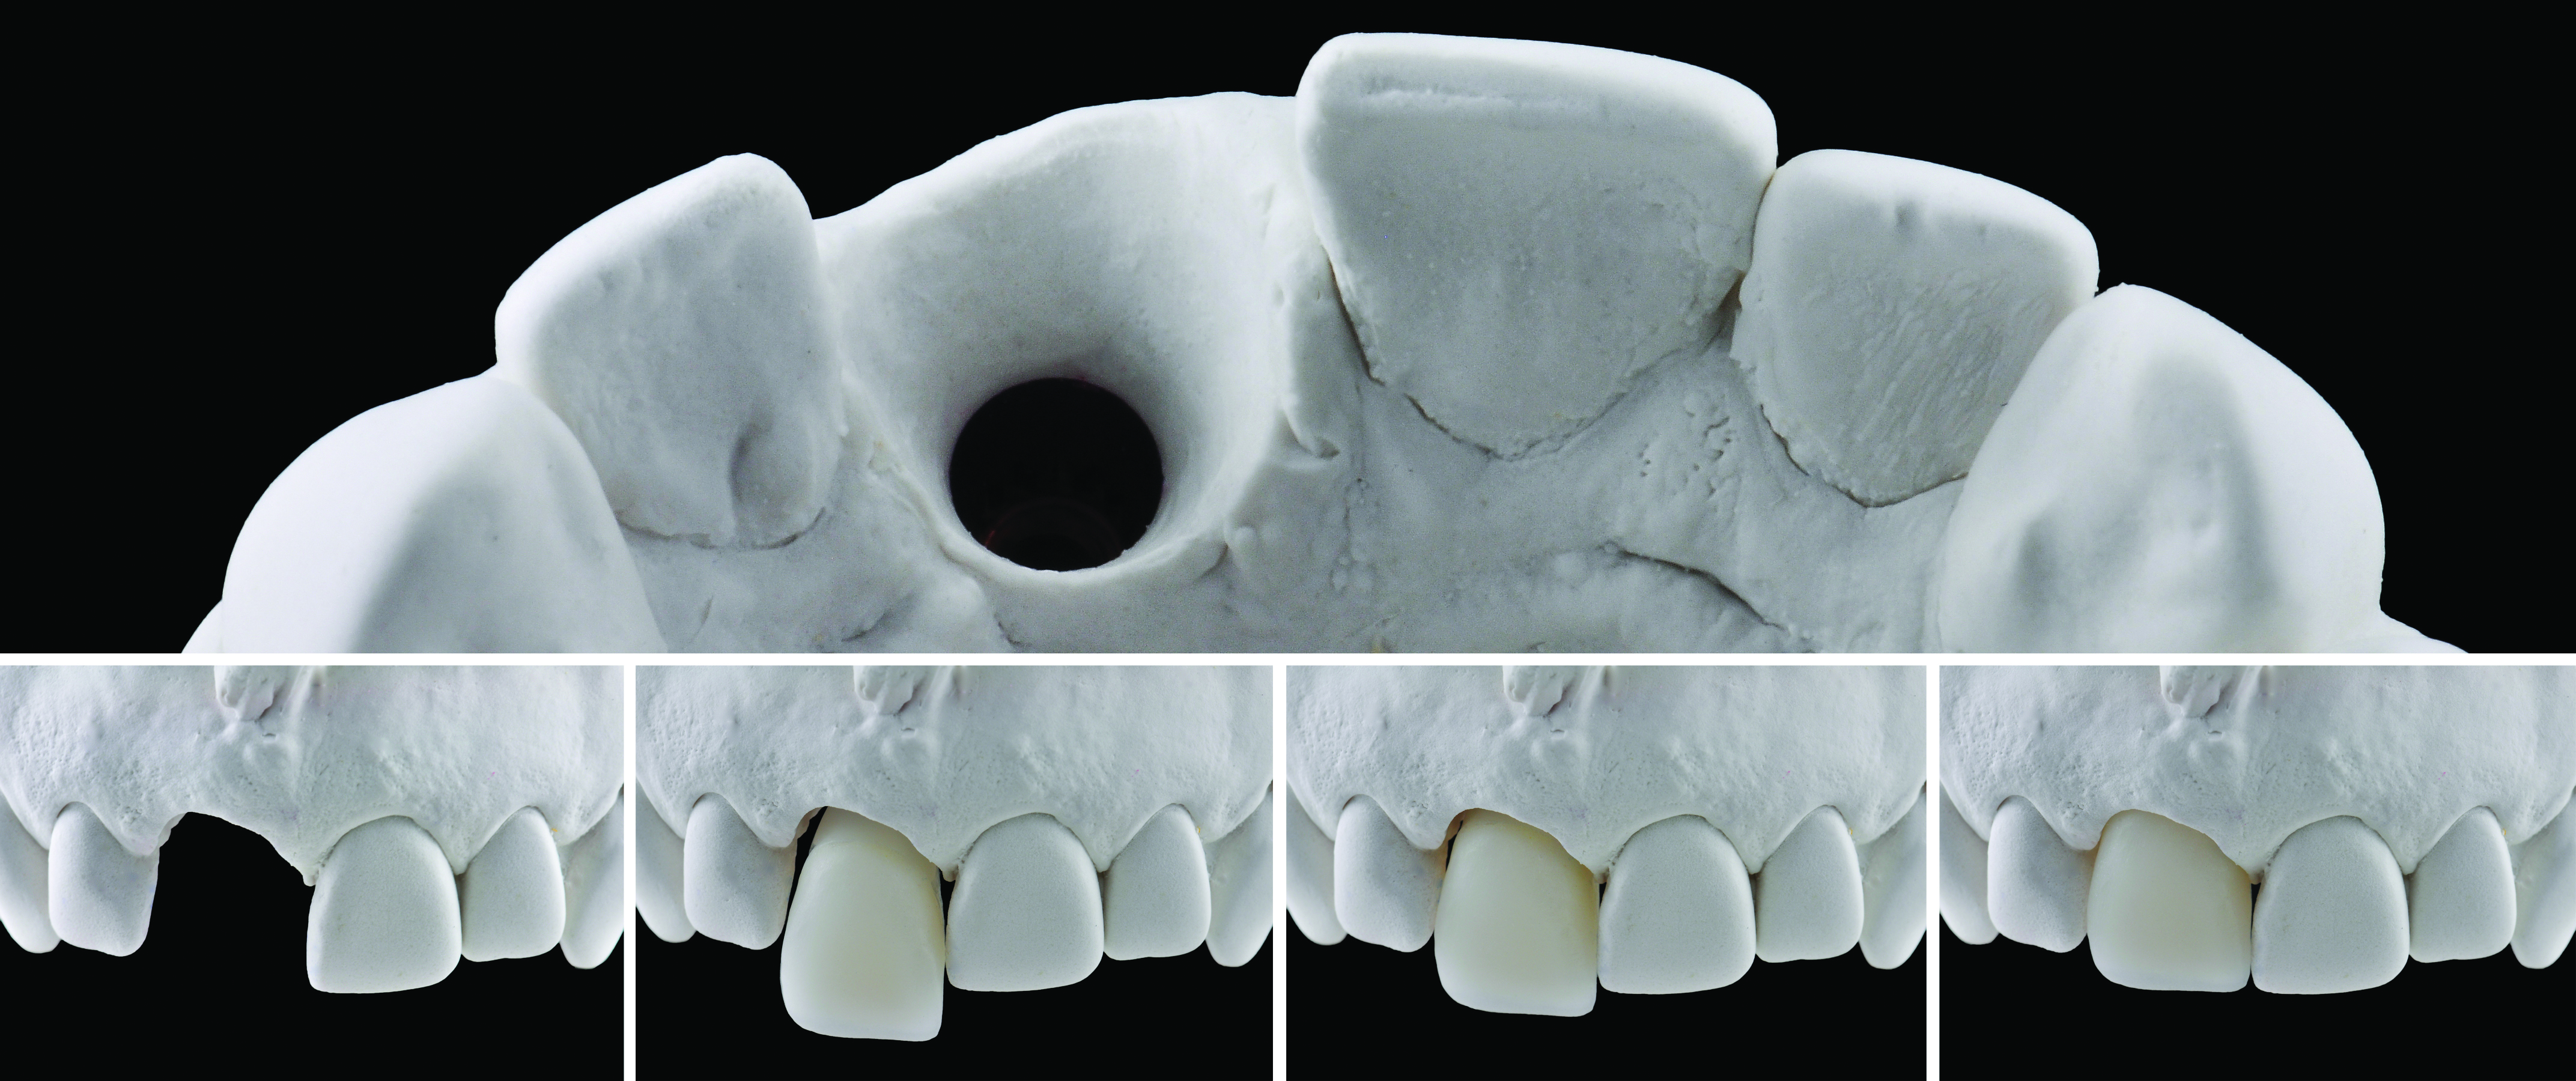

Fig 7. The master cast demonstrating the mature peri-implant sulcus, allowing the technician to design an optimal emergence profile and coronal contour to match the adjacent central incisor.

Figure 7

The maxillary master cast was poured in type IV stone (ResinRock, Whip Mix Corporation, whipmix.com) and scanned with a laboratory-based scanner (Lava™ Scan ST, 3M ESPE) to digitize the master cast. The resulting digital dataset was imported into the ATLANTIS WebOrder software, and a proposed abutment design was sent for review based on the author’s prescription of a zirconia, screw-retained CAD/CAM abutment (ATLANTIS Crown Abutment). Some minor alterations to the initial design of the abutment were made in ATLANTIS 3D Editor, which the technician confirmed prior to milling (Figure 6). Subsequent to milling at the ATLANTIS production facility, the abutment was sent to the technician for application of veneering porcelain (Cerabien ZR, Kuraray Noritake Dental Inc., kuraraynoritake.com) based on a custom shade analysis completed earlier by the technician (Figure 7).